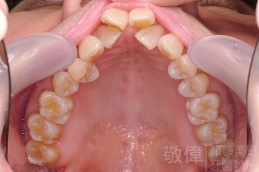

齒顏矯正/上顎暴牙且牙齒極度混亂

矯正前-右   矯正前-正   矯正前-左

矯正前-上   矯正前-下

矯正後-上   矯正後-下

<個案說明>

上顎暴牙且牙齒極度混亂,經由矯正之後,臉型大幅度改善,牙齒的排列更加的整齊健康。相較於之前眼神充滿精神,自信心展現無遺。